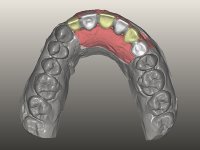

Foi aconselhada a extracção dos dentes 12 e 11 e esperar mais 3 meses para se conseguir uma completa cicatrização da zona. Estabilizada a situação fazer-se –ia um enceramento de diagnóstico que dando origem a uma guia imagiológica permitiria fazer uma TAC. em que o posicionamento idealizado dos dentes pudesse ser relacionado com o património ósseo. O objectivo seria fazer uma ponte cerâmica implanto suportada.

O paciente foi observado conjuntamente e a dúvida que surgiu de imediato foi se seria possível com a regeneração óssea a efectuar poder ser reabilitada naturalmente a zona das papilas interdentárias. Nesse sentido foi feito um enceramento de diagnóstico que contemplaria as duas hipóteses, utilizando ou não a cerâmica gengival. A confecção desse enceramento foi fundamental para expor ao paciente a dificuldade da reabilitação. O wax-up deu origem a um mock-up que foi aprovado pelo paciente e que simultaneamente serviu de guia imagiológica. O caso foi planificado cirurgicamente e realizada uma guia cirúrgica com que foram colocados os implantes. Após 10 semanas foi feita a 1ª impressão para confecção da ponte provisória. Foram criados os primeiros perfis de emergência na gengiva artificial e foi digitalizado o modelo. Por processo de CAD-CAM foi confeccionada uma ponte provisória aparafusada baseada no enceramento de diagnóstico. A ponte trabalhou durante 8 semanas os tecidos moles que foram fielmente copiados numa impressão com técnica de moldeira aberta. Os transferes foram individualizados com resina composta para copiarem fielmente os perfis de emergência criados pela ponte provisória. Confeccionado o modelo de trabalho definitivo, foi realizada uma infra-estrutura em zircónio seguindo a orientação do enceramento de diagnóstico. O assentamento da infra-estrutura foi testado em boca e simultaneamente foi novamente impressionados os tecidos moles com um silicone fluido. Nessa consulta foi feito o levantamento da cor. Os dentes 13 e 23 apresentavam uma saturação anormalmente forte que resolvemos não valorizar, optando por privilegiar a relação com o sector antero-inferior. Foi realizada uma nova gengiva artificial com a impressão que acompanhou a impressão de arrasto com a infra-estrutura. Após a colocação da cerâmica na infra-estrutura foram coladas as meso-estruturas. O trabalho final foi aparafusado lentamente permitindo a adaptação dos tecidos moles.